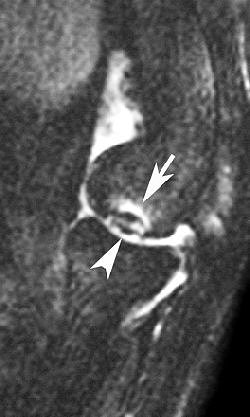

| Sagittal MRI of JOCD on 1.5-tesla scanner. Protocol included FSE and T2-weighted imaging (TR/TE 3500/55). Image courtesy of Dr. Nancy Major, Duke University Medical Center, Durham, NC. |